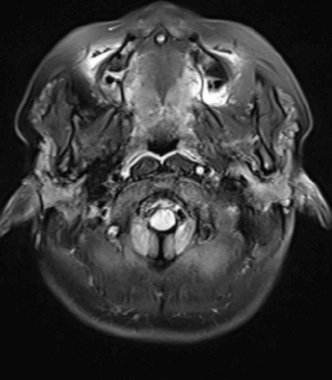

颅脑MR(水抑制)

发病第三日完善了颅脑MR检查:左侧大脑半球脑梗死(病灶新旧不一) 。

完善高分辨MR检查:左侧大脑中动脉M1局部偏心性强化。